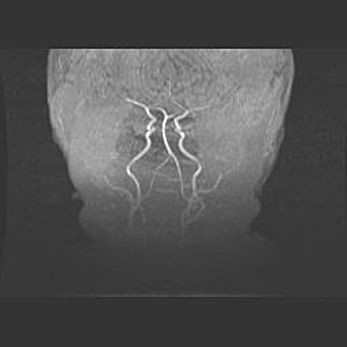

Мальформация Денди-Уокера. Киста задней черепной ямки.

Агенезия мозолистого тела.

Возраст: 2,5 месяца

Вес: 2420 г

Пол: женский

Окружность головы: 37 см

Срок гестации: 32 недели

Мальформация Денди—Уокера — редкий вид патологии ЦНС, представляющий собой врожденный порок развития каудального отдела ствола и червя мозжечка, ведущий к неполному раскрытию срединной (Мажанди) и латеральных (Лушка) апертур IV желудочка мозга. Для этогно синдрома характерна триада симптомов: гипотрофия червя мозжечка и/или полушарий мозжечка, кисты задней черепной ямки, гидроцефалия различной степени. В 70% случаев порок сочетается и с другими аномалиями головного мозга, в частности с агенезией мозолистого тела.